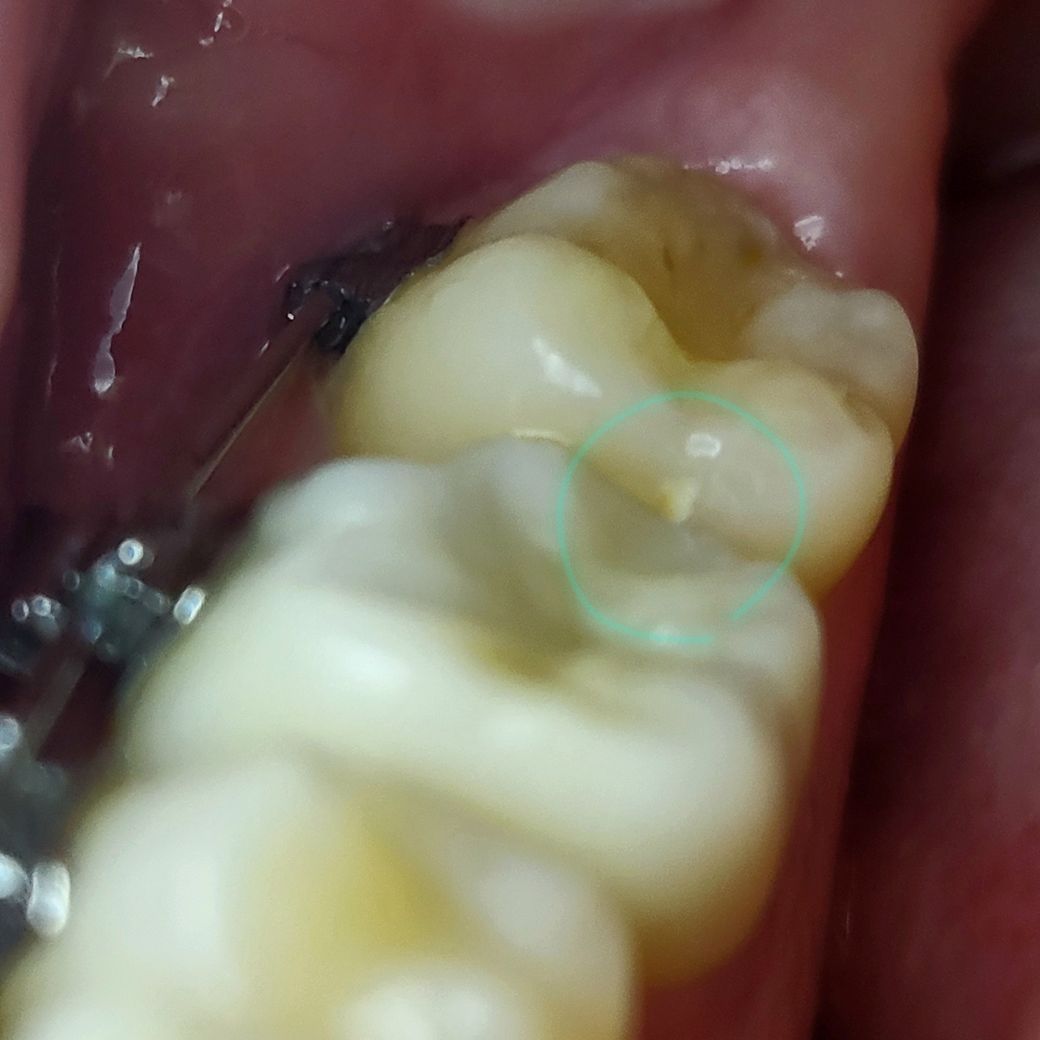

최근 제일안쪽 어금니 인접면에 하얀충치가 발견되어 네비게이터로 긁어보니 진행중인 충치가 맞았고, 진료중인 치과에서는 레진으로 하면 좋겠으나 위치가 어렵다고하여 일단 놔둔 상태입니다..

설측에 가까운 위치인데 각도가 안나와서 레진이 어려운건지..?

해당 부위가 충치가 맞기는 하나 기구가 접근하기 매우 어렵습니다. 즉 인접부위에 충치가 생기게 되면 치질 삭제가 과도하게 이뤄져야 합니다. 다만 해당 부위가 초기 충치인지 아니면 진행되었는지에 따라 개선될지는 다를 수 있어 보입니다. 따라서 조금 더 지켜보시고 충치가 계속 진행한다면 인레이 등으로 치료를 계획하셔야 할 것으로 보입니다

인접면에 충치가 생겨 있습니다.

그냥두면 점점 밑으로 그리고 옆으로 충치가 진행되니 빨리 치료해야 합니다.

그리고 인접면 충치의 경우 바로 뒤의 치아에도 충치가 잘 생깁니다.

사진상에서도 바로 뒤의 어금니 인접면의 충치도 의심됩니다.